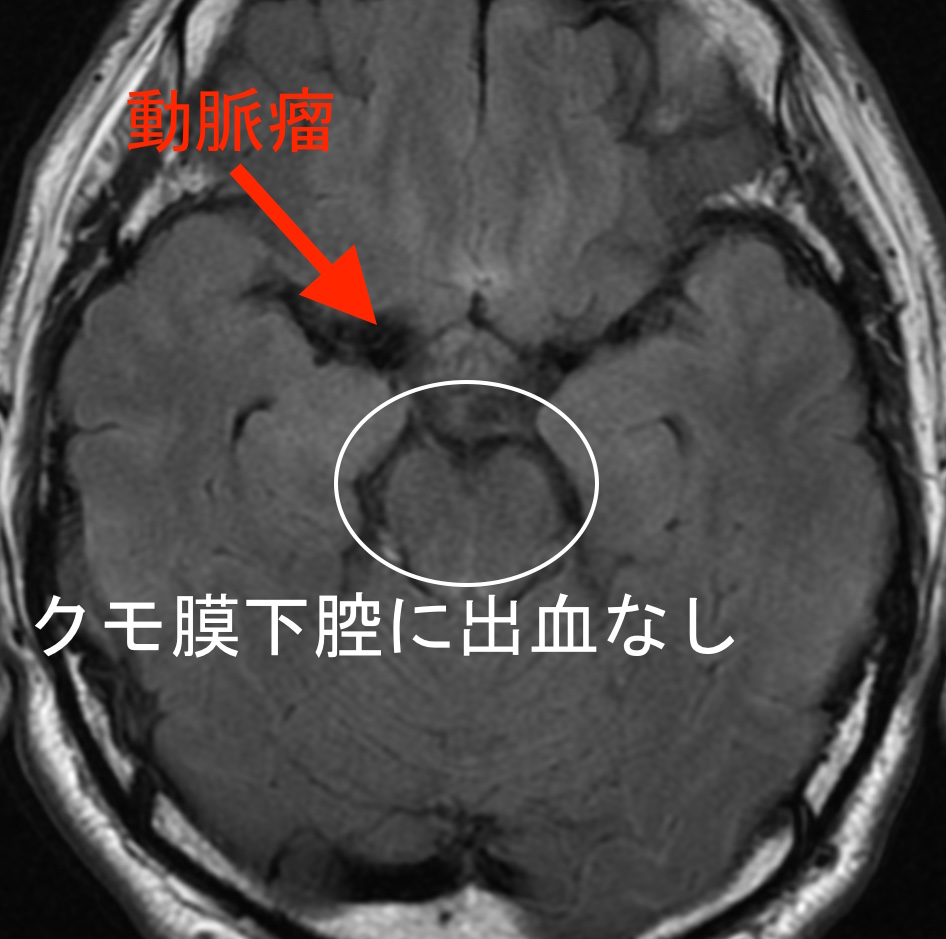

頭部の断層画像でも、今回出血した形跡はありませんでした。

くも膜というのは、頭蓋骨とその内側の硬膜という固い膜のさらに内側にある薄い膜で、くもの巣のように見えるのでそう呼ばれています。

くも膜下腔という脳の表面全体に出血が拡がり、頭蓋骨内部の圧力(脳圧)が急激に上昇するため脳が圧迫され、突然死もあり得る病気です。